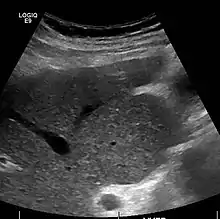

Imaging

Ultrasound is routinely used in the evaluation of cirrhosis.[34] It may show a small and shrunken liver in advanced disease. On ultrasound, there is increased echogenicity with irregular appearing areas.[51] Other suggestive findings are an enlarged caudate lobe, widening of the fissures and enlargement of the spleen.[52] An enlarged spleen, which normally measures less than 11–12 cm (4.3–4.7 in) in adults, may suggest underlying portal hypertension.[53] Ultrasound may also screen for hepatocellular carcinoma and portal hypertension.[34] This is done by assessing flow in the hepatic vein.[54] An increased portal vein pulsatility may be seen. However, this may be a sign of elevated right atrial pressure.[55] Portal vein pulsatility are usually measured by a pulsatility indices (PI).[54] A number above a certain values indicates cirrhosis (see table below).